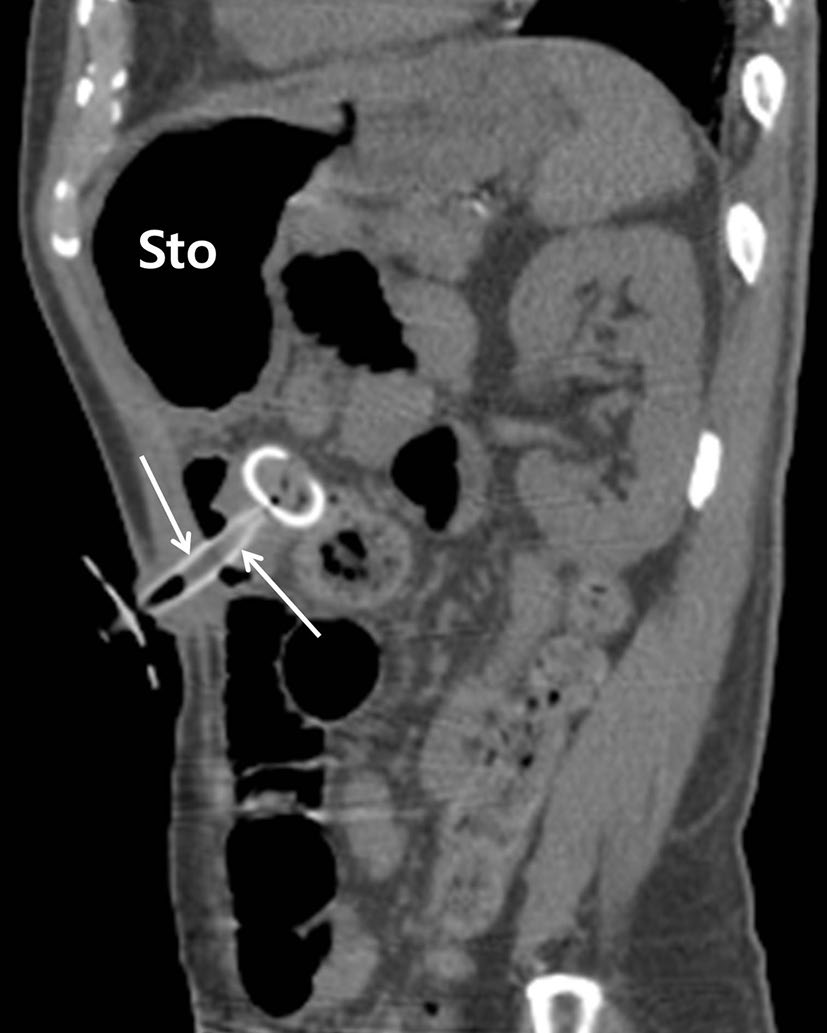

输尿管支架

输尿管支架通常用于治疗输尿管梗阻或瘘(图4)[7]。支架的近端和远端部分设计为J形或猪尾形,以防止从输尿管迁移。然而,由于蠕动作用,支架仍可能发生迁移(图5)[7]。